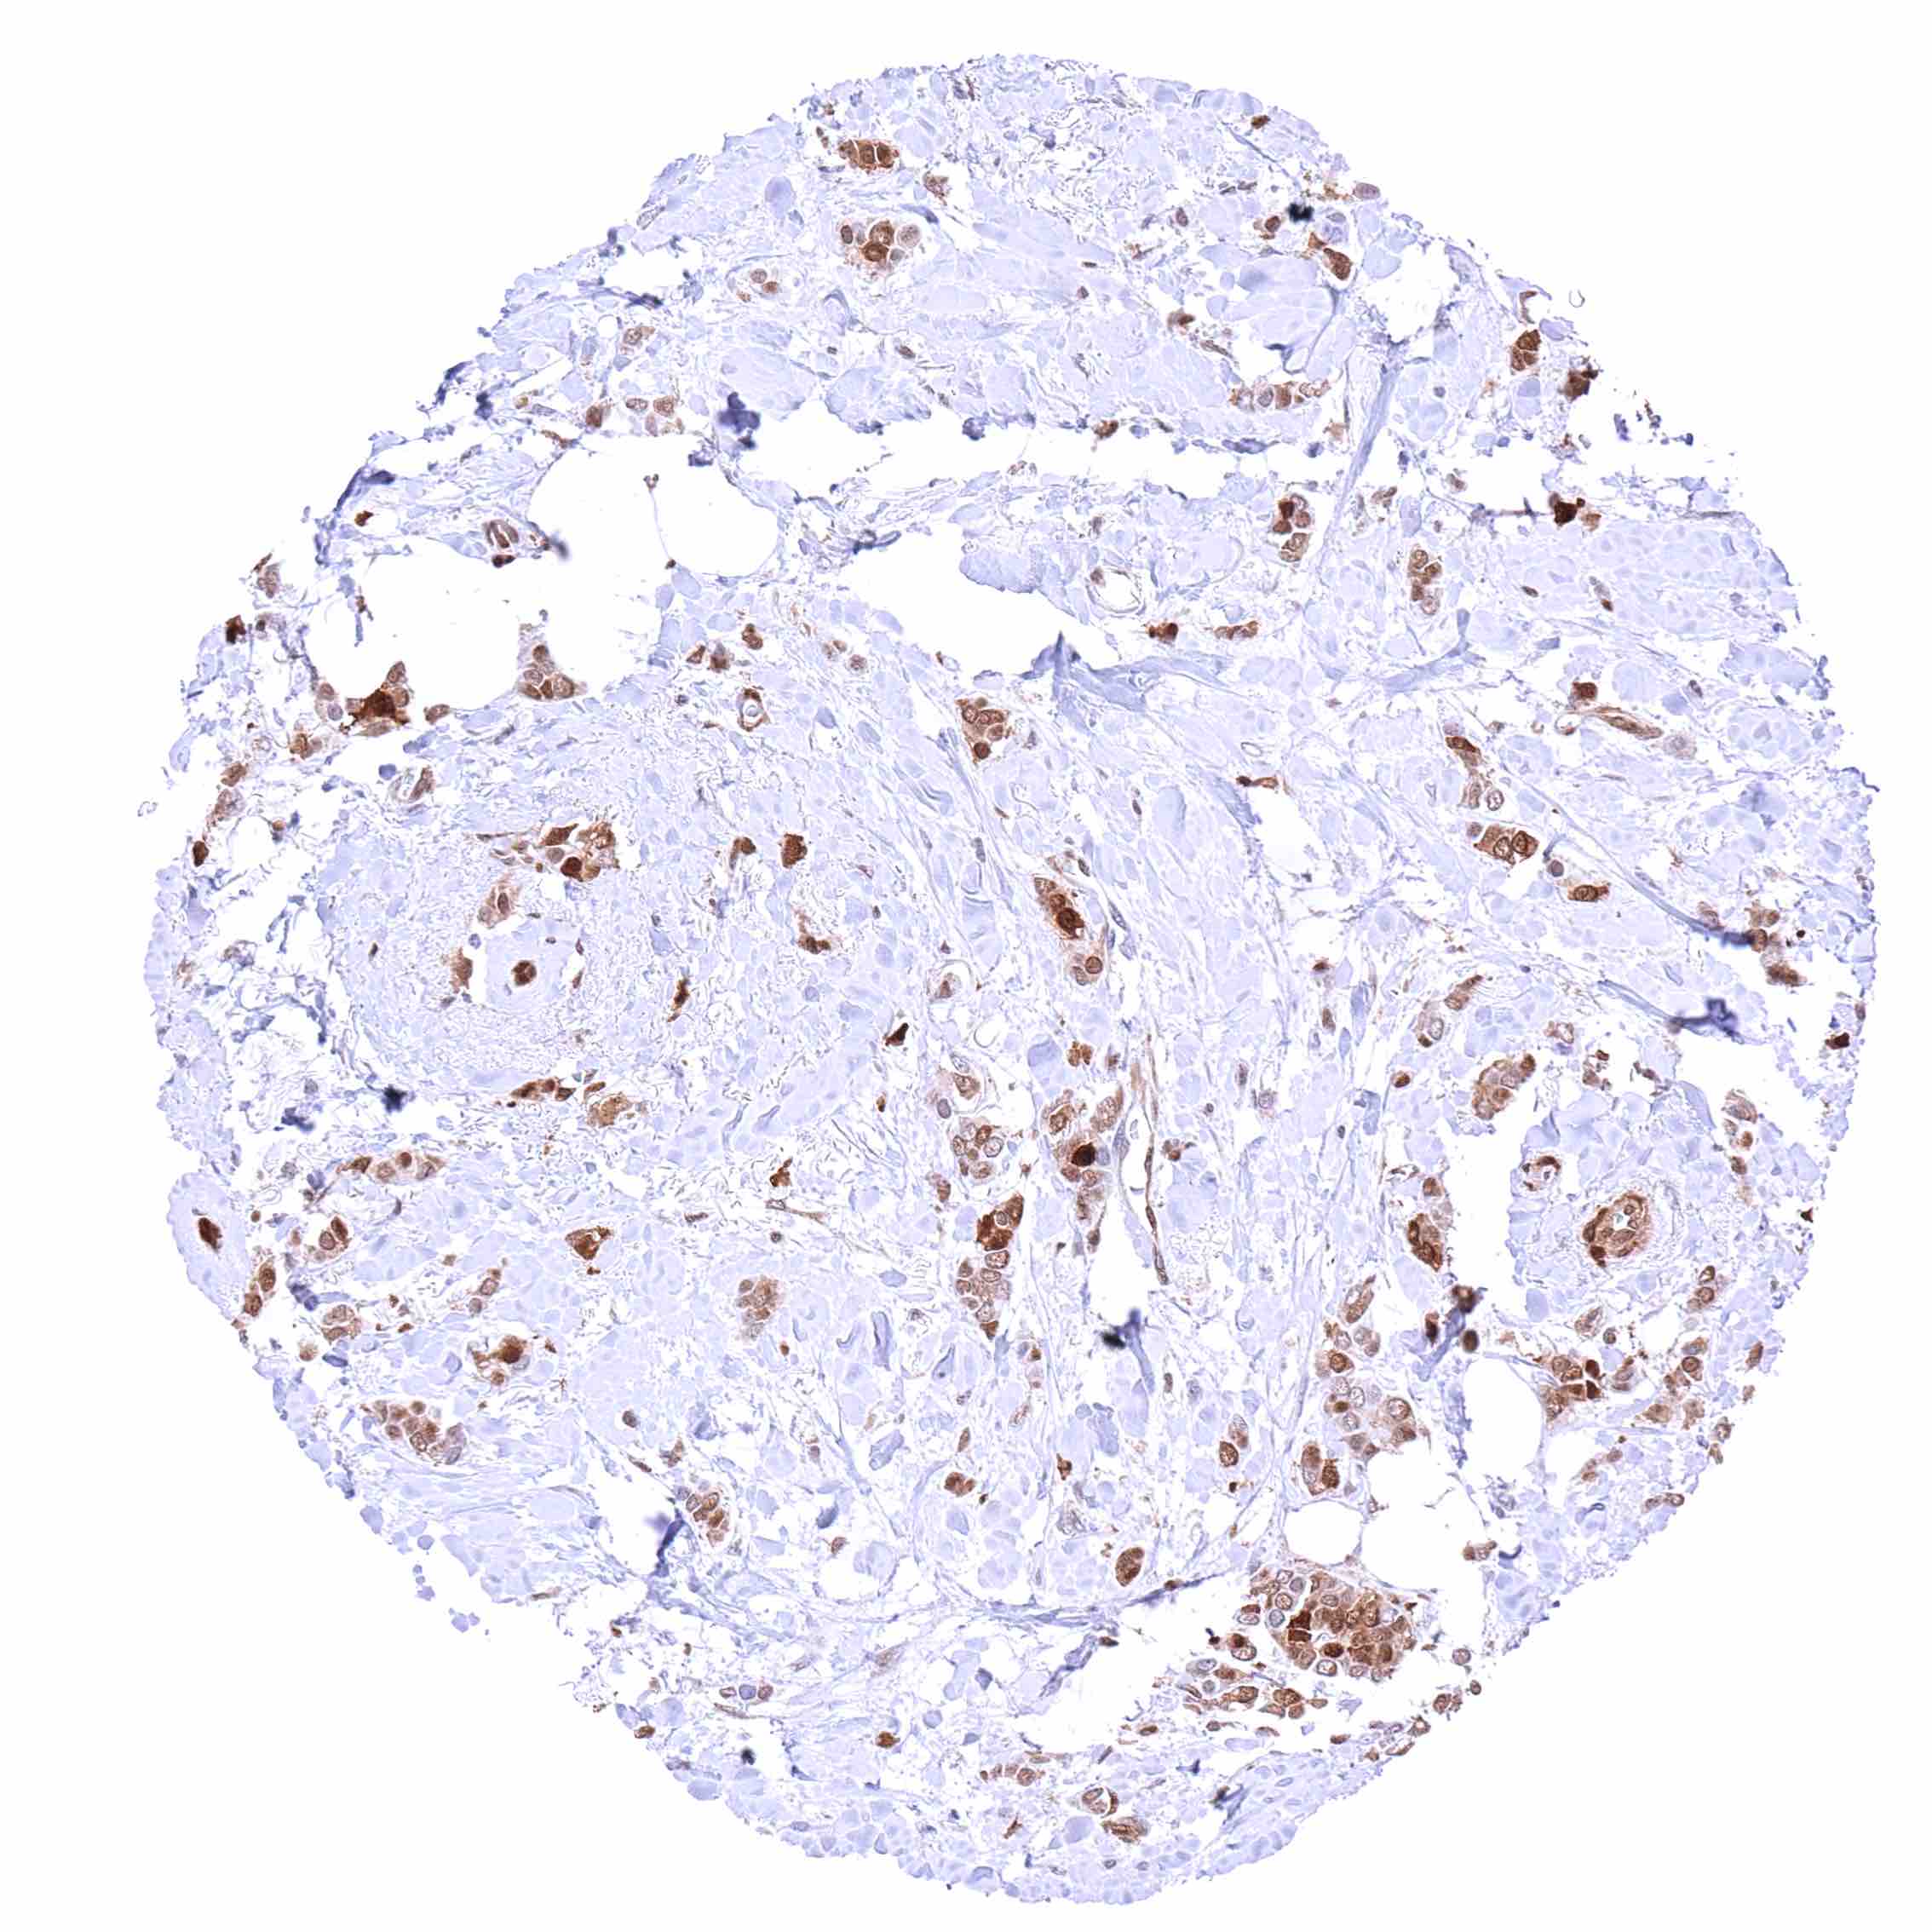

Lung – Adenocarcinoma with faint p27 staining of few tumor cells. Strong p27 positivity of stroma cells.